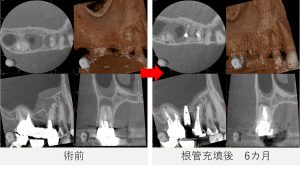

根管充填後6か月

- レントゲン写真およびCT撮影を行い、経過を確認しました。

- 治療前に認められていた、根尖部から遠心側方にかけて広がっていた黒い影は、大幅な改善が認められました。

- これらの結果を踏まえ、今後はご紹介元のかかりつけ歯科医院にて、最終的な被せ物を作製していくこととなりました。